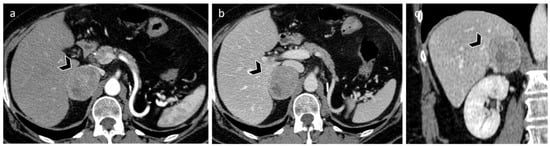

3.3. Carcinoma